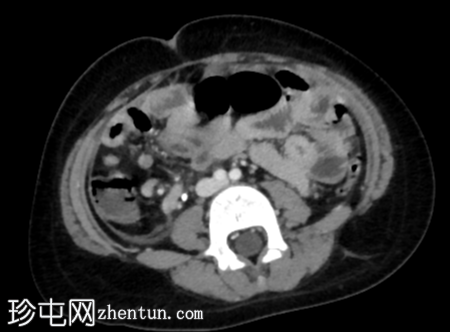

CT

轴位增强扫描(门静脉期)

阑尾扩张,壁增厚并强化,周围阑尾周围脂肪组织条索状改变。

阑尾尖端近端可见局灶性壁缺损。

该缺损旁可见一小环状强化积液。

结肠周围及肠系膜区可见多个肿大淋巴结。

腹膜增厚。

影像

学表现符合急性阑尾穿孔的诊断,阑尾尖端近端可见局灶性壁缺损。环状强化积液提示阑尾周围脓肿。

术中发现证实了影像诊断,阑尾发炎,阑尾尖端近端有壁缺损,阑尾周围区域有脓液积聚。